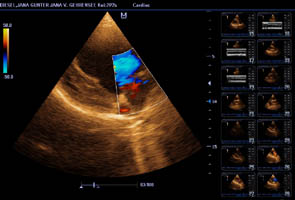

Herzultraschall von Lena vom Gehrensee zur Vermeidung von DCM

Durch Klick auf die Übersicht können die Herzdaten eingesehen werden.

Der Herzcheck ergab keinen Hinweis auf DCM.